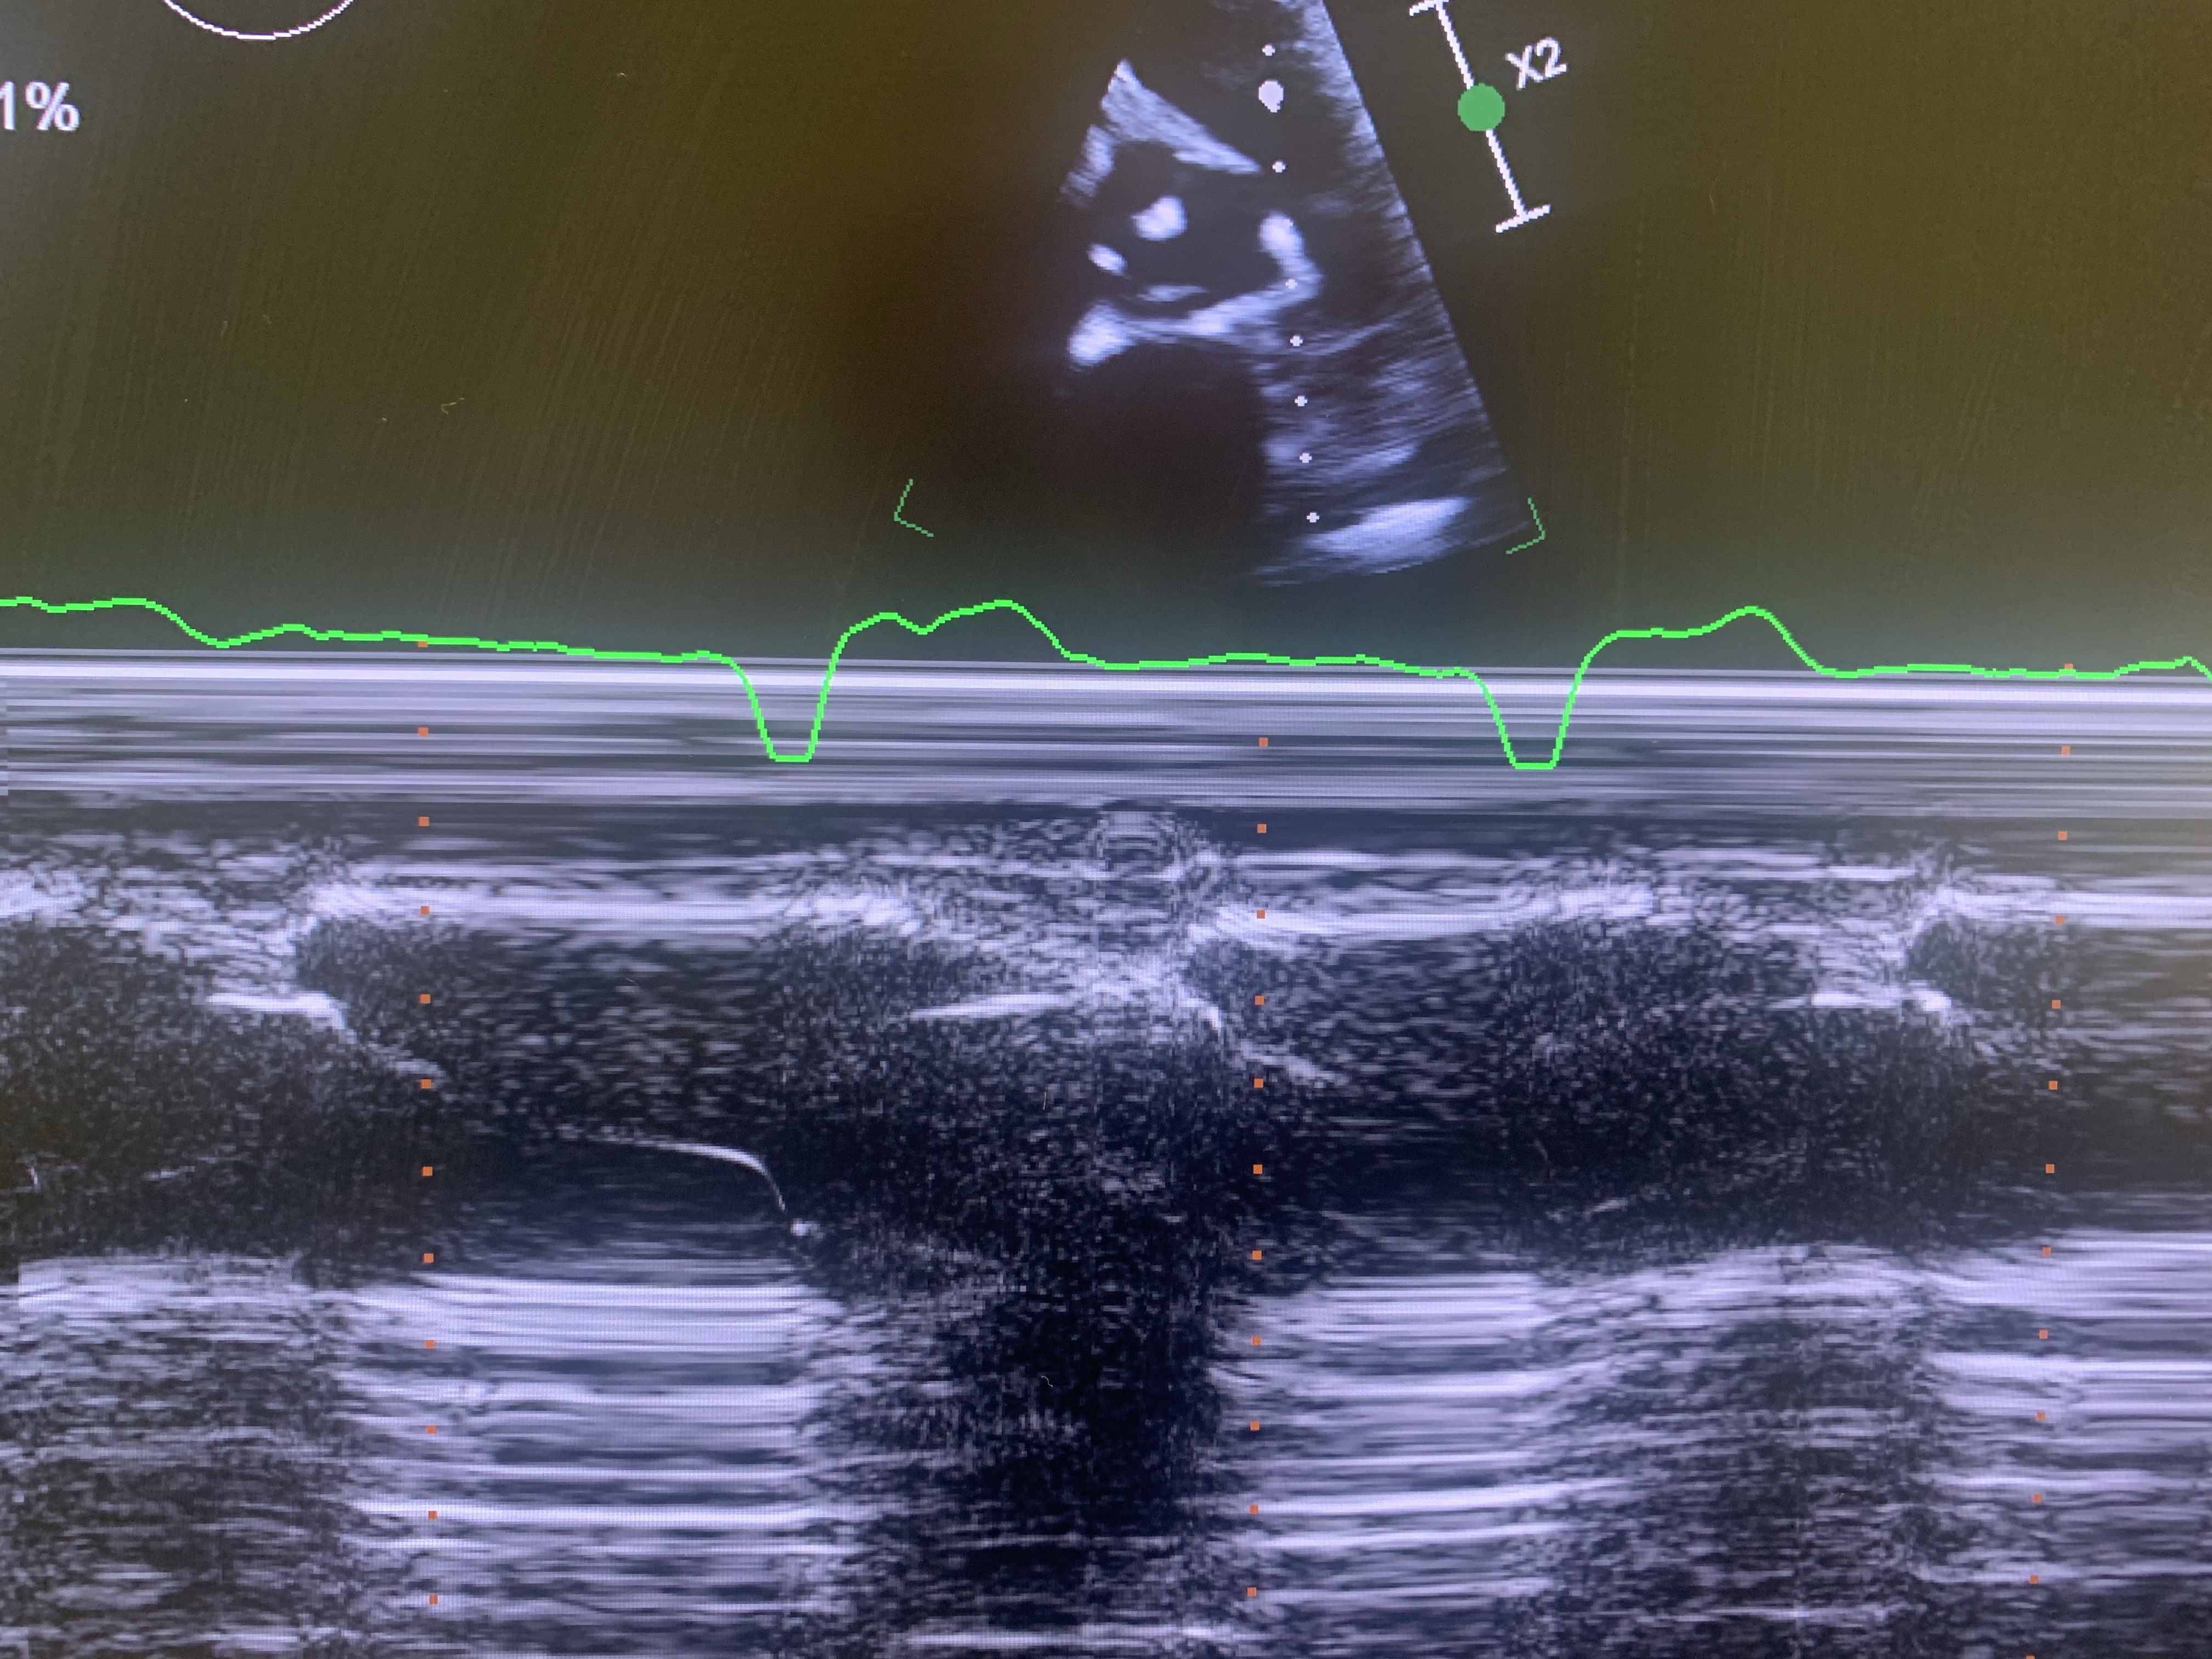

Adults with this condition don’t need surgical intervention (most of the time). However, adults with a repaired TOF, the VSD patch is evident on echo, aortic root is enlarged and there’s so evidence of residual RV outflow obstruction. The major issue is late pulmonic regurgitation.

During echo, make sure to get a good view of the aorta and the aortic root. Measure in parasternal long axis view. If possible, obtain a few extra images. Use pulsed or CW Doppler signal to look for diastolic reversal of flow equal in signal strength to antegrade flow (pulmonic regurgitation). Obtain a good RV images (RV focused view) and make sure to see the endocardium well. If the patient had a VSD repair, obtain extra images in A4 and Sub4 at the level of ventricular septum. Use PW and CW in Sub4 to make sure there’s no leakage after the repair.